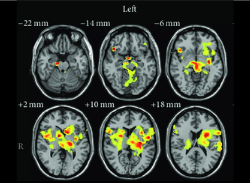

L’immense majorité de la recherche en acupuncture porte sur son degré d’efficacité à traiter certaines conditions de santé, en particulier dans le domaine des douleurs musculo-squelettiques. La publication de résultats en recherche fondamentale ces dernières années, notamment en neurologie, font aussi avancer notre compréhension scientifique des mécanismes d’action potentiellement impliqués en acupuncture.